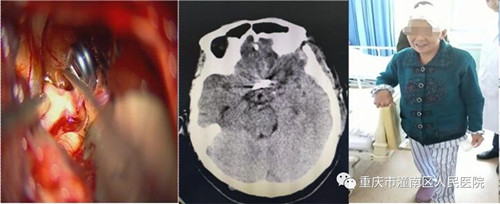

患者家属们在认识到动脉瘤破裂出血的突发性及其严重性后要求手术治疗。在谭超主任带领及重医大附一院钟东教授的指导下,成功在全麻下经左侧翼点入路行前交通动脉瘤瘤颈夹闭术。手术顺利,术后患者神志恢复清楚,语言、肢体功能均顺利恢复,步行出院。

该患者是动脉瘤二次破裂出血,再次陷入昏迷,病情紧急危重,命悬一线。颅内动脉瘤夹闭手术是神经外科手术中风险和难度最大的手术之一,我科医务人员对该前交通动脉瘤进行夹闭术后,患者恢复良好。该手术的再次成功开展标志着小艾电竞社区